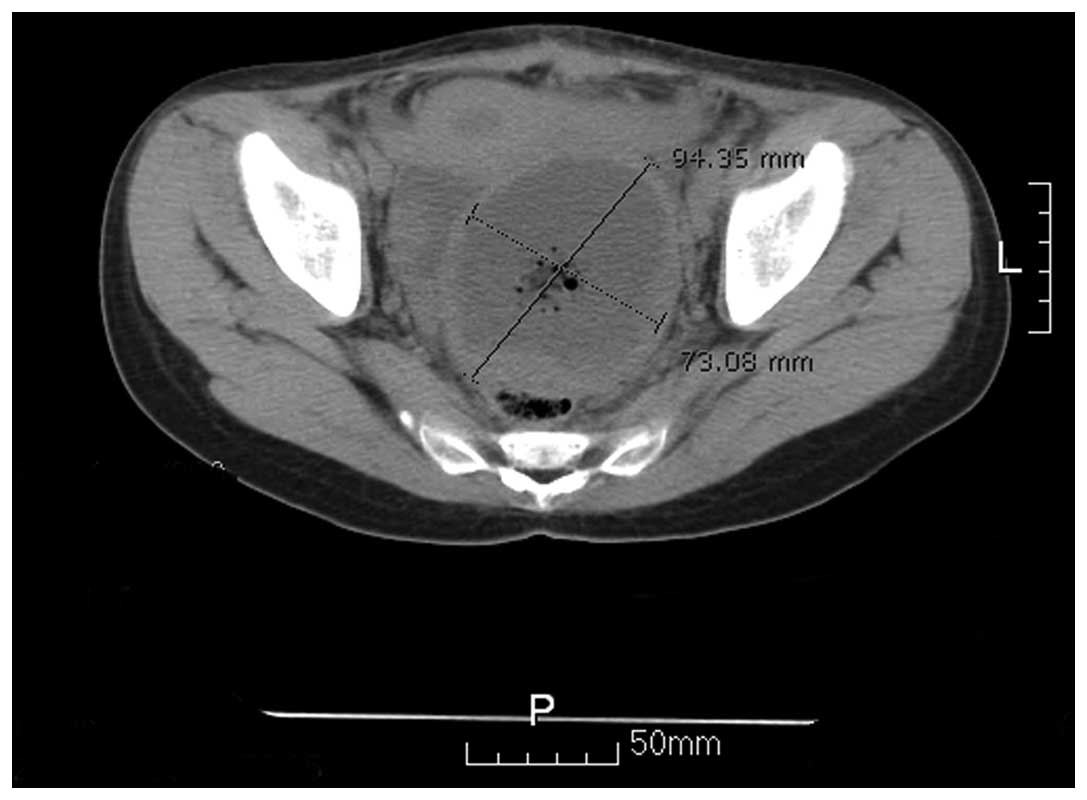

Following two cycles of chemotherapy consisting of bleomycin (15 mg for three consecutive days), etoposide (150 mg for four consecutive days) and cisplatin (40 mg for three consecutive days; termed a BEP regimen), the serum AFP levels decreased to 1,251.27 ng/ml on January 7, 2010 and the CT scan revealed that the tumor size had significantly reduced (Fig. 2). The interval debulking and fertility-sparing surgeries (unilateral left side salpingo-oophorectomy, omentectomy and intumescent lymph node resection) were performed on January 12, 2010. No residual tumor was found and the histopathology report showed a marginal quantity of tumor tissue in the pelvic floor and no positive lymph nodes (Fig. 3). Following surgery, an additional two cycles of chemotherapy, consisting of the aforementioned BEP regimen, were administered continuously. Following surgery and an additional two cycles of the BEP regimen, the serum AFP levels decreased to 8.17 ng/ml following the final administration of the BEP regimen on February 28, 2010.

Figure 2

Computed tomography scan of the tumor. The size of the mass was 4.6×5.0 cm, which was significantly reduced compared with Fig. 1.